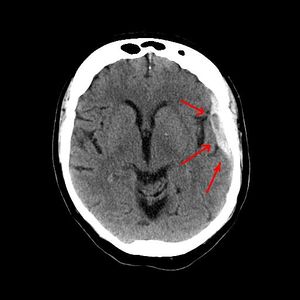

| Appearance on CT | Biconvex lens | Crescent-shaped |

يعتمد رئيساً على تصوير الدماغ (التصوير الطبقي المحوري والرنين المغنطيسي MRI)، وفيه يظهر النزف عادة على شكل تجمع هلالي بين الجمجمة والدماغ.